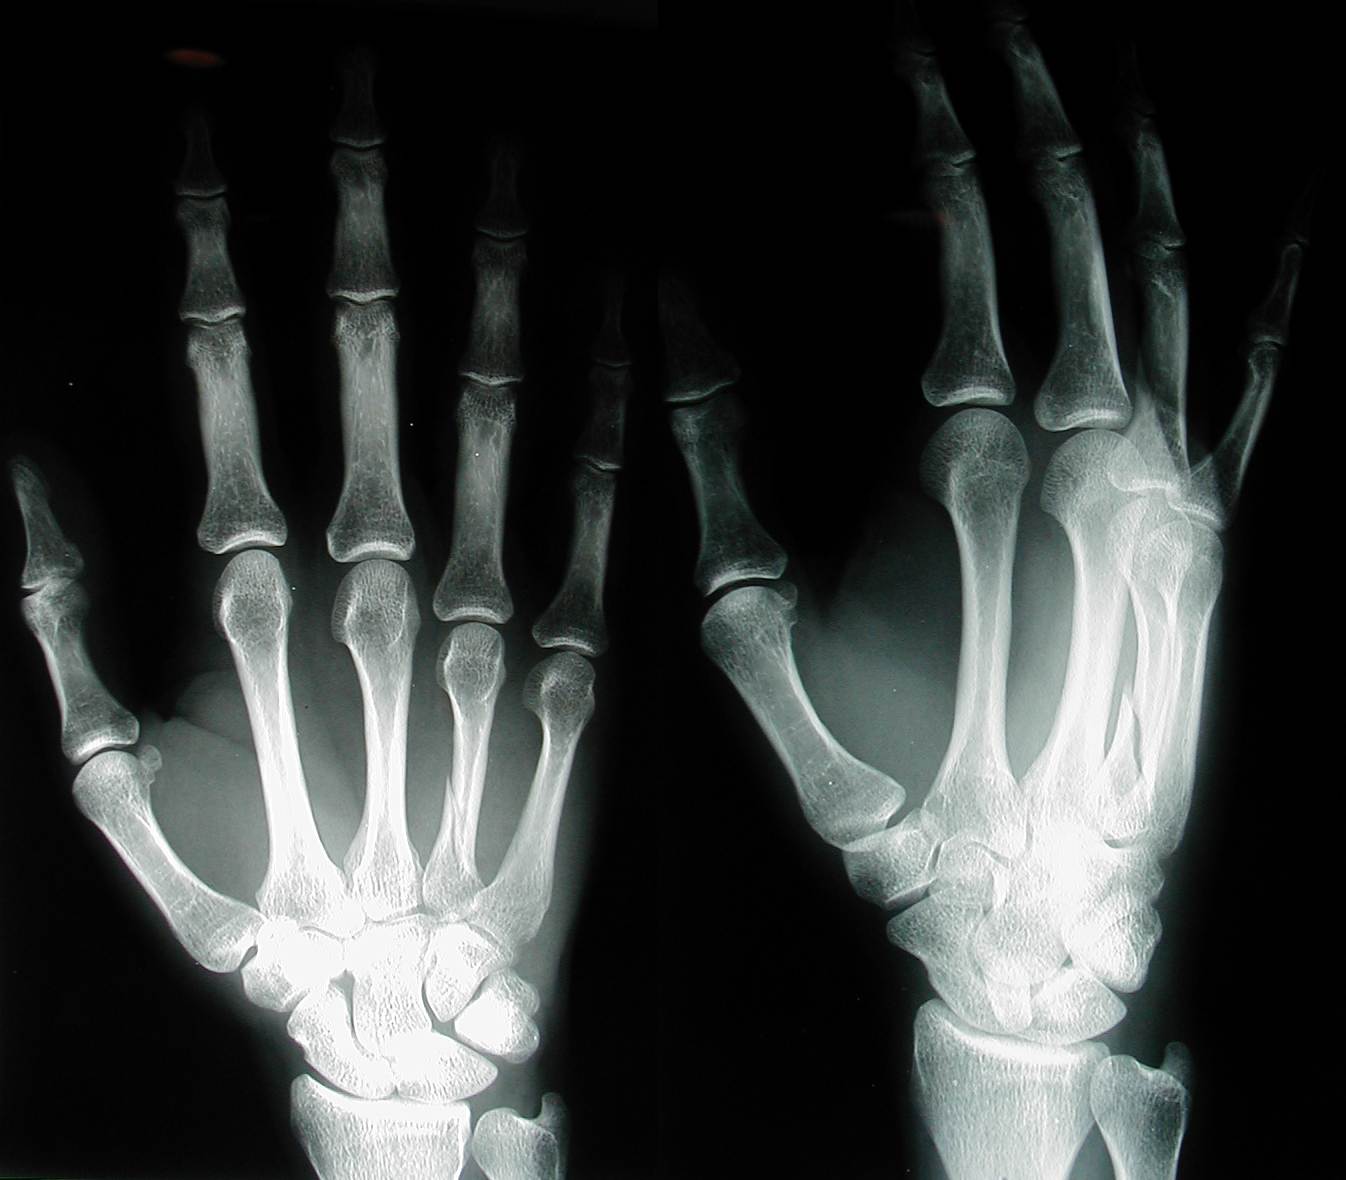

That last trick proved truly stupid when on the way down in a twist something in my left hand made a loud SNAP! accompanied by, shall we say, pain. I quietly excused myself from the human circus and wandered off to poke and prod at my hand to see if I could figure out what I did to it--with the unfortunate conclusion that I'd broken the metacarpal bone of my left ring finger.

Having run out of options, I went to Palo Alto Medical Center's urgent care so I could at least get an x-ray to find out if I was just being a wuss. I asked for copies of the x-ray on the spot, knowing they'd be hard to get later. The tech said she'd take the primaries first and copy them if there was anything wrong. She copied them. (It proved fortuitous later that I was holding my own copies--it got me in to see the orthopod same day instead of three to five days later...)

Apparently this sort of break is a common consequence of twisting a hand. First time I've actually broken a bone. I fractured a wrist bone once skateboarding, but it was just a crack, not a bifurcation.

Before I could protest, there was a nurse in the room making up another temporary splint, no better than the one I had walked in with. God knows how much they'll charge me for that one, or for the slightly longer half-plaster one the ortopedist upstairs made me two hours later as he amusingly chewed on his protruding tongue while cinching down the wrap so tight that half way back to Tahoe my fingers turned purple and my hand started cramping (you can bet that felt good; I had to drive the rest of the way with my hand over my head until I got home and re-wrapped it myself). So, basically I got a set of x-rays and a slightly better splint for... I am guessing $800 to $1000? (I wonder how this would have transpired in New Zealand?) So I'm missing a hand for the next month or two, and I'm told to expect my ring finger to be a little shorter than it used to be. Oh well, it's all getting recycled eventually anyway.